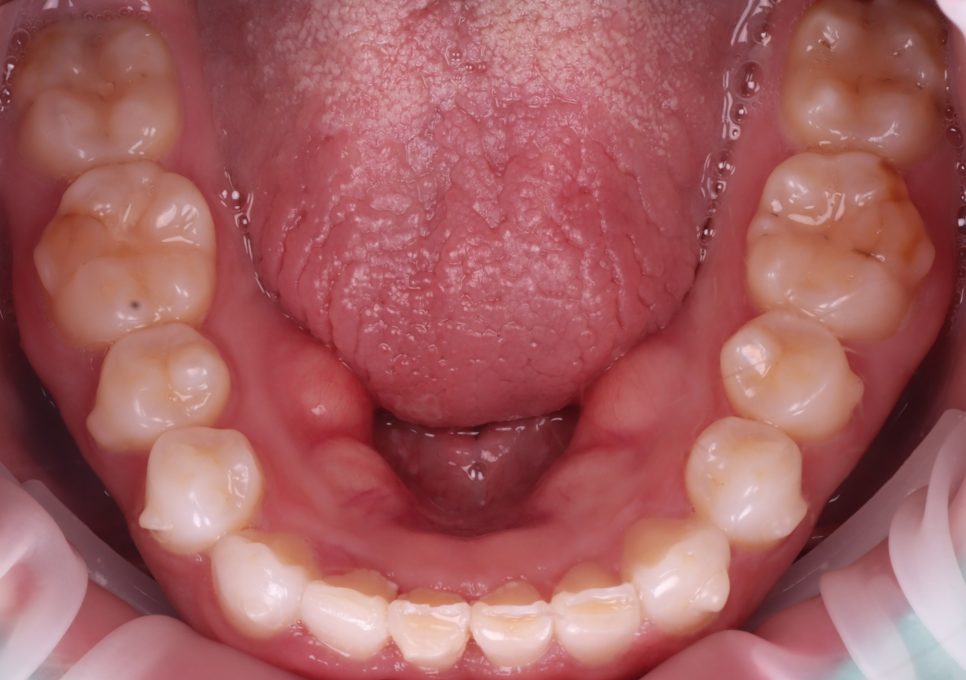

아래 앞니는 전체적으로 교모(씹으면서 생긴

닳은 것)이 심했는데 일단 위 앞니를 먼저

해결하기를 원하셔서 지켜보기로 했습니다.